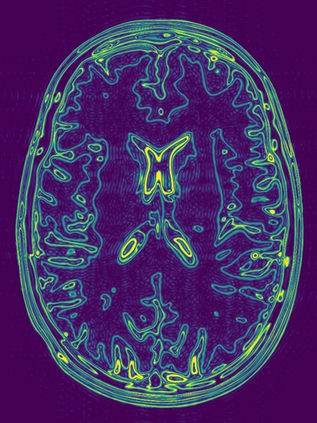

Implicit neural representations (INRs) have emerged as a powerful tool for solving inverse problems in computer vision and computational imaging. INRs represent images as continuous domain functions realized by a neural network taking spatial coordinates as inputs. However, unlike traditional pixel representations, little is known about the sample complexity of estimating images using INRs in the context of linear inverse problems. Towards this end, we study the sampling requirements for recovery of a continuous domain image from its low-pass Fourier coefficients by fitting a single hidden-layer INR with ReLU activation and a Fourier features layer using a generalized form of weight decay regularization. Our key insight is to relate minimizers of this non-convex parameter space optimization problem to minimizers of a convex penalty defined over an infinite-dimensional space of measures. We identify a sufficient number of samples for which an image realized by a width-1 INR is exactly recoverable by solving the INR training problem, and give a conjecture for the general width-$W$ case. To validate our theory, we empirically assess the probability of achieving exact recovery of images realized by low-width single hidden-layer INRs, and illustrate the performance of INR on super-resolution recovery of more realistic continuous domain phantom images.